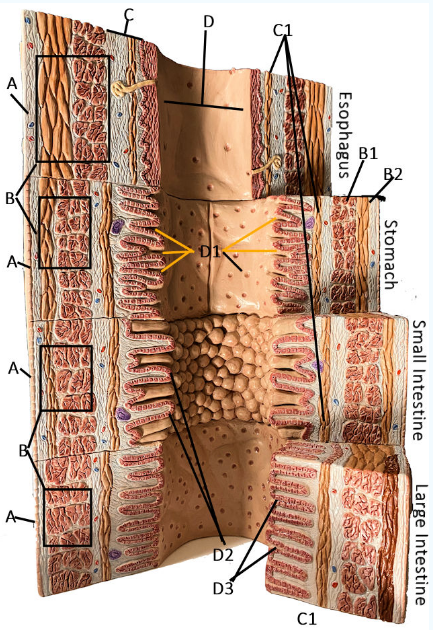

A

Serosa

B Esophagus

Muscularis externa: skeletal, skeletal/smooth, and smooth, circular and longitudinal

B Stomach

Oblique, circular, and longitudinal smooth muscle

B Small intestine

circular and longitudinal smooth muscle

B large intestine

circular and longitudinal smooth muscle

C

Submucosa: areolar and dense connective tissue

D

Lumen

D1

Gastric glands/pits

D2

Villi of small intestine

D3

Intestinal crypts of large intestine